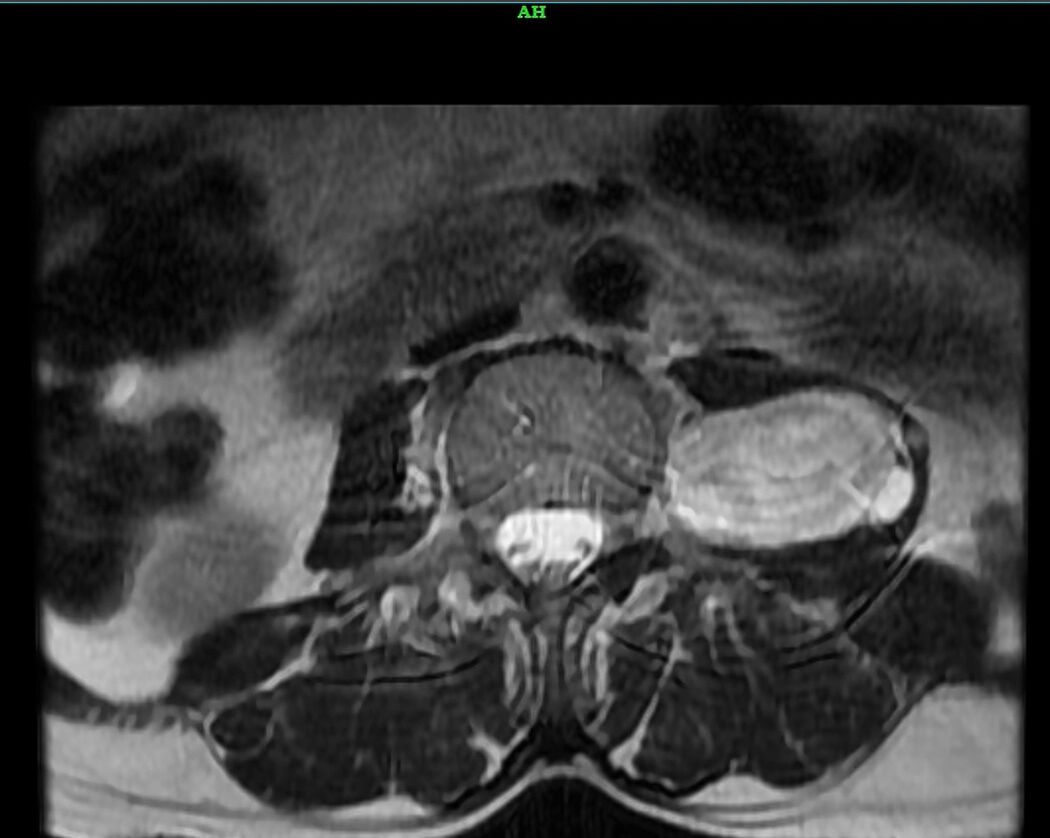

Laparoscopic Removal of Lumbar Paraspinal Schwannoma | Dr Pavan Kumar

A 50-year-old woman presented with a left lumbar paraspinal schwannoma, a benign nerve sheath tumor located deep in the retroperitoneal space. MRI revealed two well-defined lesions measuring 10 × 5 cm, extending from L2 to L5, with no intracanalicular extension. She successfully underwent excision of the tumor through a transperitoneal minimally invasive approach, which provided excellent visualization, precise dissection, and safe tumor removal.

Although retroperitoneal masses are often considered a relative contraindication for laparoscopic surgery, in this case the patient underwent safe paraspinal mass removal with no intraoperative complications, minimal blood loss, and faster recovery compared to conventional open surgery.

The postoperative course was uneventful; the patient recovered smoothly and was discharged on the 4th postoperative day without neurological deficits or perioperative complications.